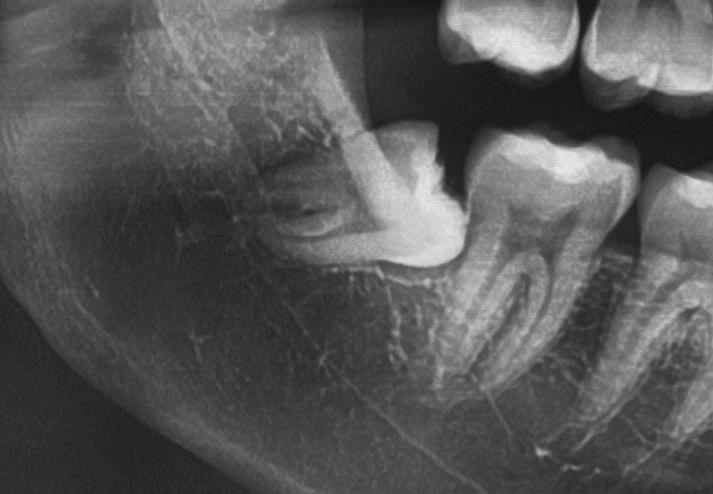

Questo è un paziente di 22 anni ed essendo un amico, ho potuto ben documentare il caso con il suo consenso: il suo dente del giudizio inferiore sinistro è stato estratto utilizzando il manipolo dritto. Figg. 143-149

Figg. 143-149 - Caso 1, paziente di 22 anni: tecnica di estrazione con divisione orizzontale utilizzando il manipolo dritto. Fig. 143 Fig. 144 Fig. 145 Fig. 146 Fig. 147 Fig. 148 Fig. 149

Dalla radiografia (Fig. 166) sembrava che il dente avesse due radici separate, quindi è stato eseguito un taglio orizzontale utilizzando il manipolo dritto per sezionare il dente a metà. Tuttavia, la corona si è frat-

turata poiché in realtà le radici erano unite e il dente non è stato sezionato completamente.

Bisogna prendere in considerazione sempre molti fattori come, ad esempio, la forma delle radici, il sottosquadro nella regione distale del secondo molare e l’osso alveolare disto-vestibolare. Se necessario la corona e le radici vengono separate intenzionalmente per estrarre il dente, proprio come in questo caso.